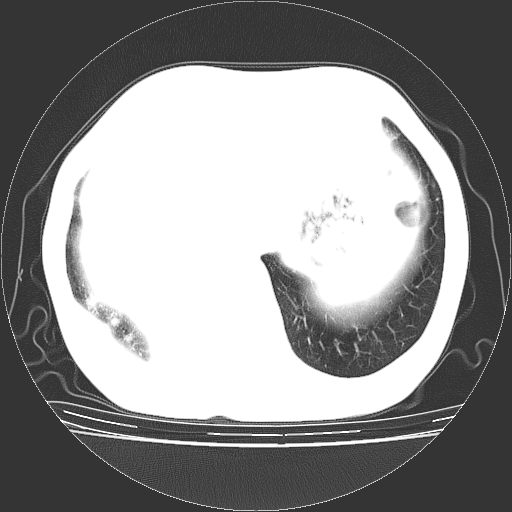

1.左上肺结核,部分纤维化。右肺中下叶部分肺不张,内见液化、坏死及点状钙化,右中下叶支气管壁增厚、管腔狭窄,见多个点状钙化,结合临床考虑支气管内膜结核,建议痰检查抗酸杆菌并参考血沉。两肺多个小圆点状高密度灶,境界模糊,多考虑结核肺内播散。但本人年龄较大首先应支气管镜检以除外右肺癌。

1、右肺占位,考虑周围型ca 。

2、右下肺软组织密度肿块影,考虑肺隔离征。

3、两肺肺结核(右肺下叶背段及左肺)。

4、主动脉夹层。

5、右侧少量胸腔积液。